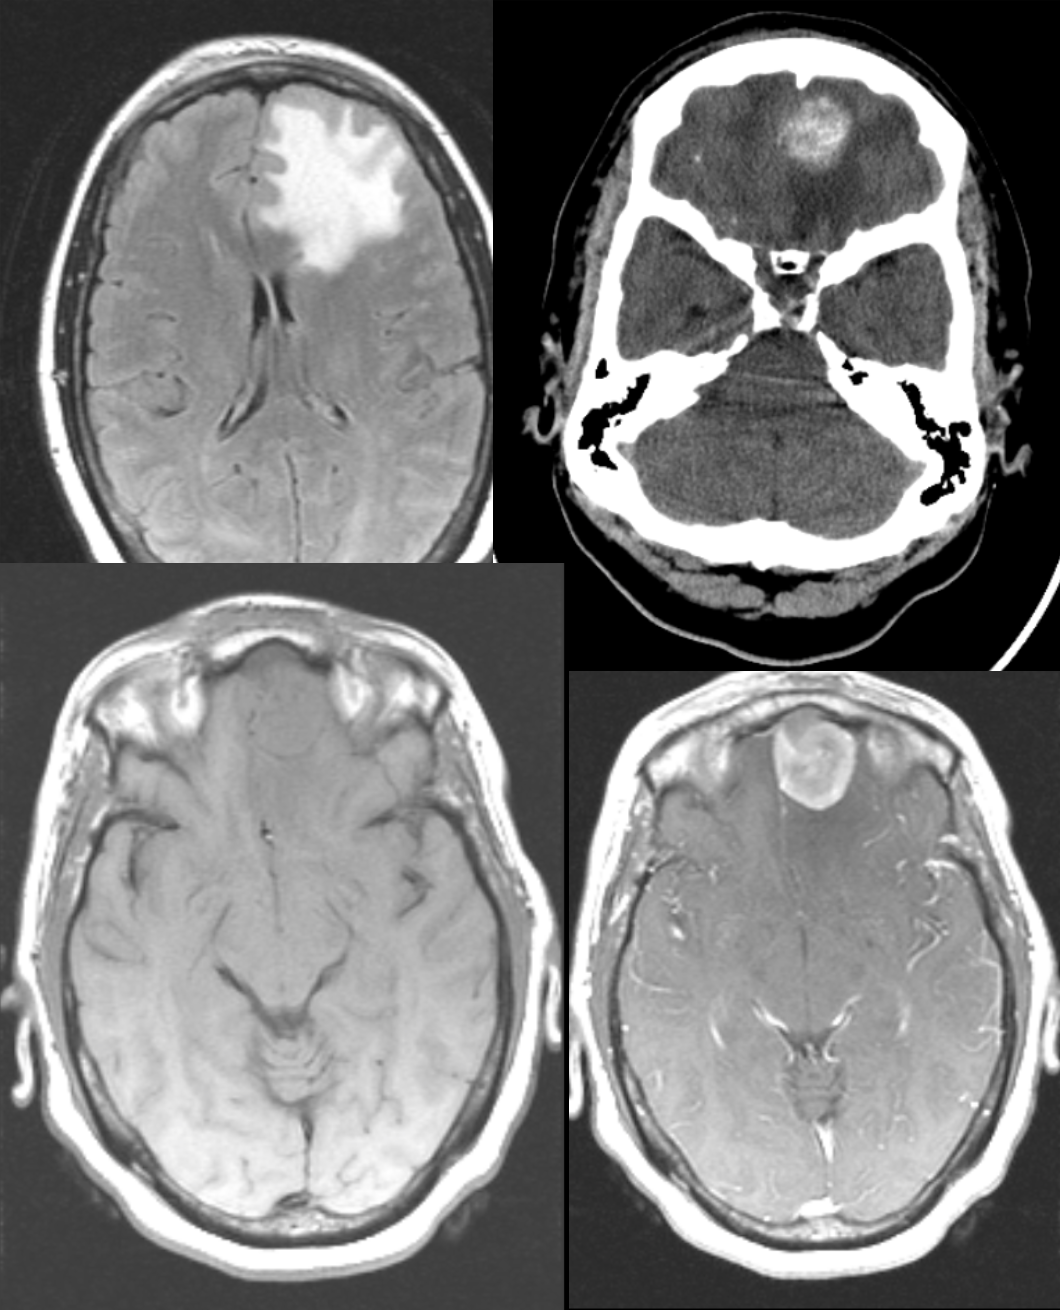

57 y/o with seizures.

Meningioma